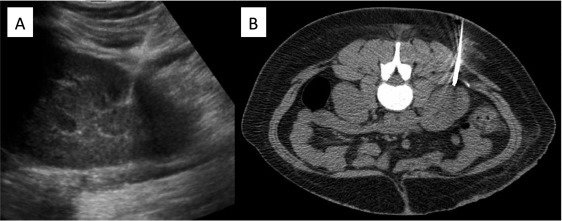

Biopsy

Indication

Preparation for Kidney Biopsy